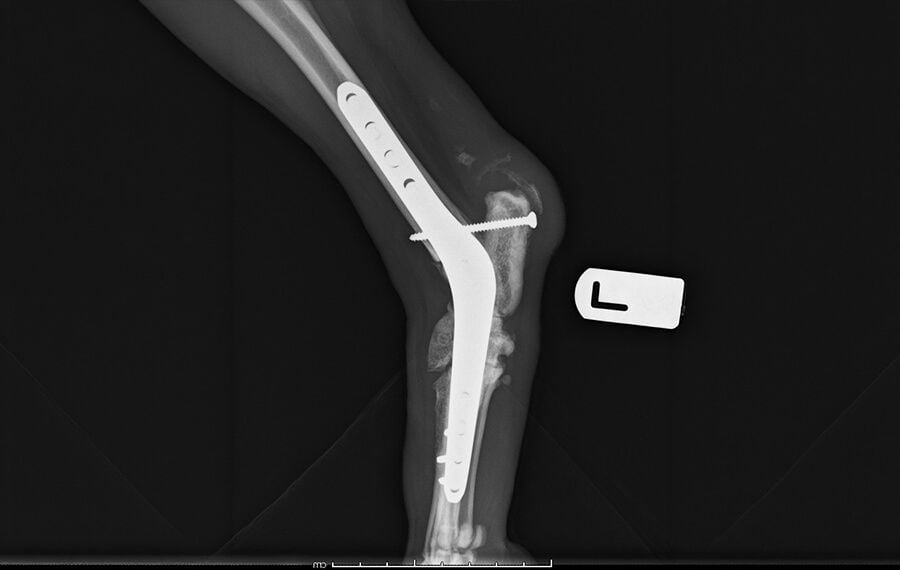

Pantarsal Arthrodesis (full fusion of the ankle)

This is the complete fusion of the tarsus, or hock (the joint between the paw and the knee).

- Appearance: This procedure has a more obvious effect on a pet's gait compared to the front limb. Because the hock is vital for "spring," the pet may have a slightly stiffer step. However, dogs and cats still regain very good mobility and are typically able to run and play happily after surgery.

- Common Indications: Performed for pets with severe hock arthritis or catastrophic injuries, such as Achilles tendon ruptures or severe ligament instability.